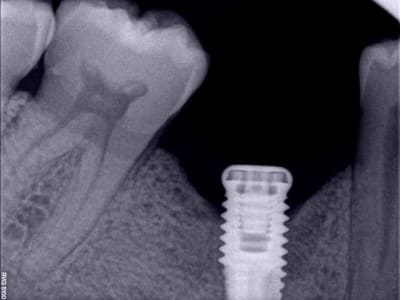

Bonjour alice, tu n'y es pour rien dans ce qui t'es arrivé. Voilà le même cas que le tien avec une importante lésion apicale sur une couronne datant de plus de 20 ans. Curetage minutieux et implantation plusieurs mois après. La suite est identique à la tienne. Sur le même patient mais sur la 36, la même lésion, même implantation et exactement la même suite. Pensant comme toi à une erreur de protocole et de toutes les salades dont on t'abreuve sur eugénol, sur la 46, j'ai remis un implant 4 mois après et même suite, j'ai compris et j'ai arrêté. C'est uniquement lié à l'infiltration de ton os par cette très vieille lésion et dont on a beaucoup parlé lors de mes formations en implanto.

Céramik, l'extraction ainsi que le curetage ont été faits un an avant l'implantation. C'était mon premier cas avec une lésion ancienne. Aujourd'hui j'ai compris et si cela m'arrive j'en parlerais des risques avec le patient.

Le but de mon post c'est d'éviter l'autoflagellation à certains de mes confrères en montrant que dans un site "douteux" comme tu dis et très ancien, on a beau prendre toutes les précautions ce n'est pas un gage de réussite et que le risque de péri implantite existe toujours malgré un bon curetage.

L'extraction a été faite en Février 2010 et la pose en Mai 2011. Quant à la crête j'avais 10mm de large et aucune table lésée. Un cas idéal.